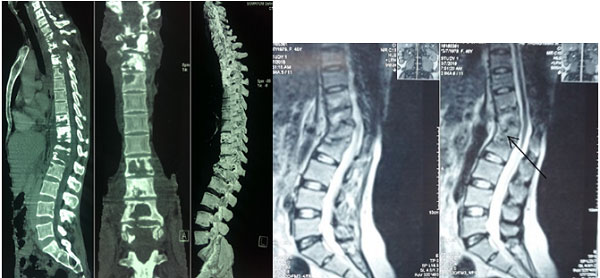

Chụp cắt lớp vi tính: thấy rõ hình ảnh tổn thương thân đốt sống, đĩa đệm, xác định chính xác độ vững của cột sống.

Chụp cộng hưởng từ: có giá trị chẩn đoán cao, giúp phát hiện tổn thương đĩa đệm, thân đốt sống, tính chất của ổ áp xe.